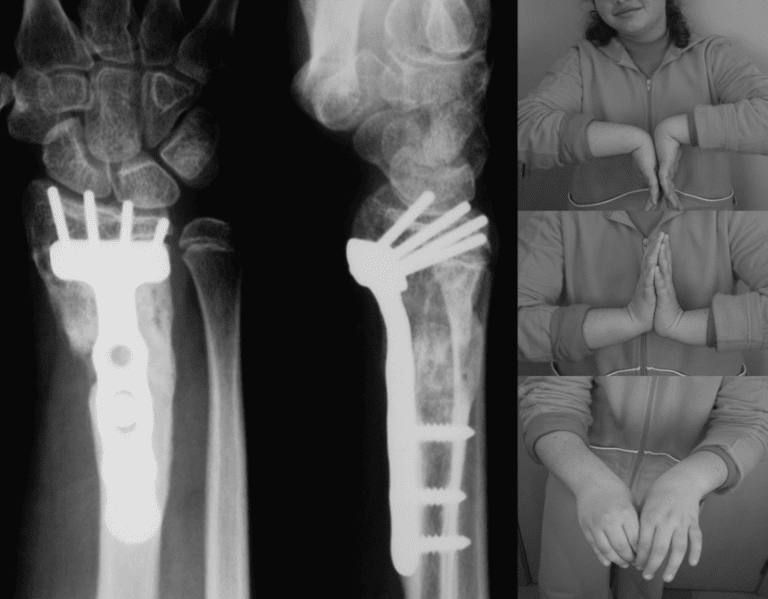

Distal radial physis closure in children can develop severe wrist deformity (radial shortening). These patients can be treated using a single-step surgery. It was carried out in the form of a corrective osteotomy adopting the volar approach, with fixed-angle volar plate fixation and bone grafting from the iliac crest.

There have been few descriptions of the use of this technique in the management of deformities related to early epiphysiodesis in distal radius. The use of fixation systems for the radius, using fixed-angle locking plates, allows radius lengthening adjusted to demand after osteotomy, using the combination of the plate and distal locking pins as spacer—with customsized tricortical iliac crest grafting within the defect.

The freeing of soft parts such as the dorsal periosteum and brachioradialis muscle tendon allows adequate bone lengthening in a single-surgical step.